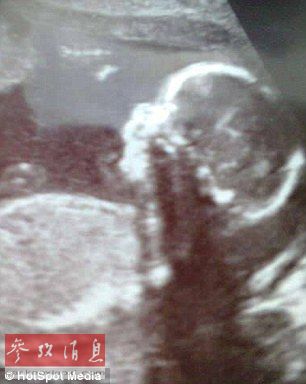

英国婴儿天生缺陷神似匹诺曹【组图】

英国婴儿天生缺陷神似匹诺曹

尽管医生在20周时提醒了母亲孩子患有缺陷的事实,但在孩子出生时母亲Amy Poole仍然被吓了一跳。